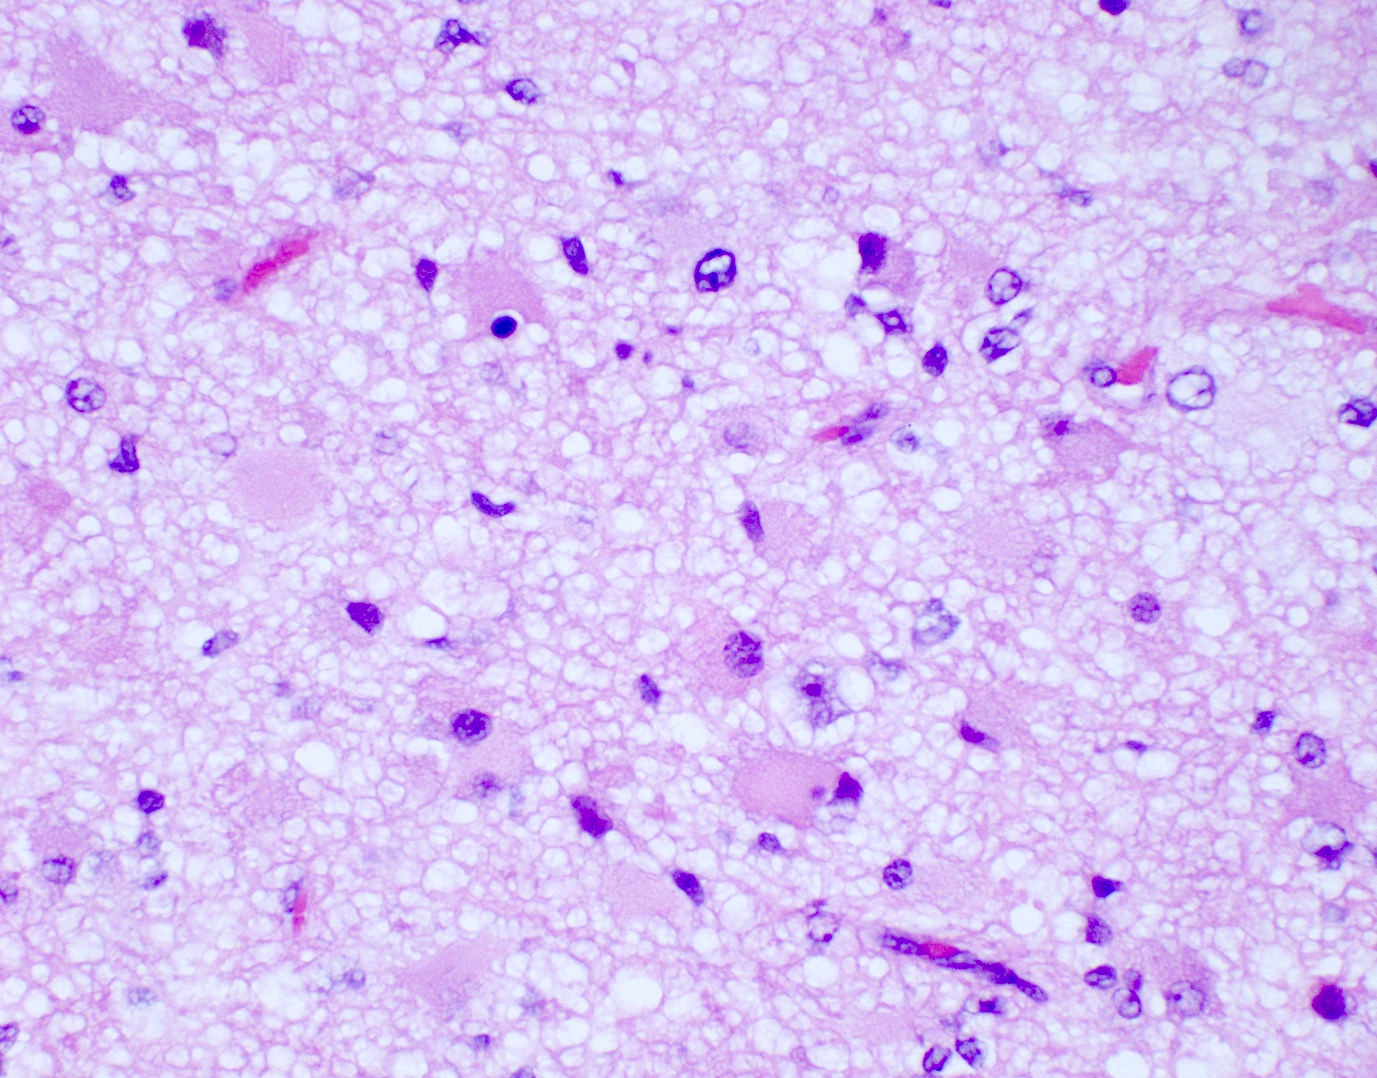

Microscopic (histologic) description

- Diffusely infiltrating tumor cells with oval to elongated astrocytic nuclei and varying appearance of tumor cytoplasm and fibrillar glial processes (Acta Neuropathol 2015;129:789)

- At the periphery, tumor cells may infiltrate in a diffuse single cell pattern, often with entrapped neurons and axons

- Cellular morphology is variable, even within a single tumor

- Commonly there is a mix of cells with elongated nuclei and fine fibrillar processes, cells with eccentric nuclei and glassy eosinophilic cytoplasm (gemistocytes), larger pleomorphic cells and small cells with scant cytoplasm

- May show oligodendroglioma-like areas

- Myxoid background and microcyst formation may be present

- Variable mitotic activity, cellularity and nuclear atypia depending on CNS WHO grade

Microscopic (histologic) images

Contributed by Eman Abdelzaher, M.D., Ph.D., John DeWitt, M.D., Ph.D. and Meaghan Morris, M.D., Ph.D.